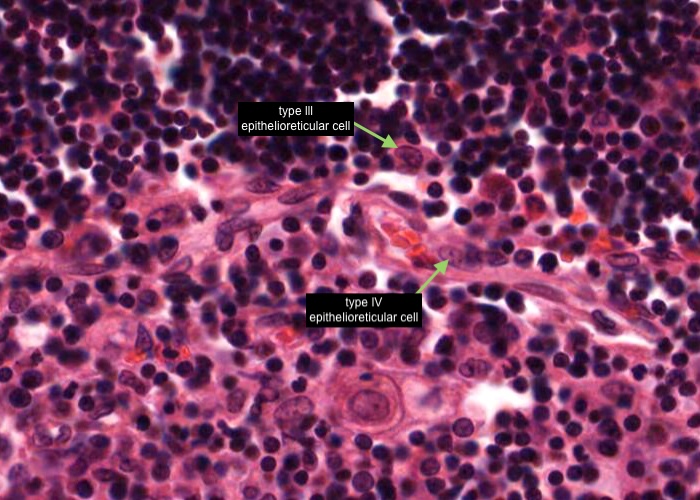

A type III epithelioreticular cell can be seen at the boundary of the cortex and the medulla. They are similar to type 1 cells in functioning as a barrier that isolates developing T- cells between the cortex and medulla.

A type IV epithelioreticular cell can be seen at the boundary of the cortex and the medulla close to the locatioons of the type III epithelioreticular cell. Together these cells interconnect and function as a barrier that isolates developing T- cells between the cortex and medulla